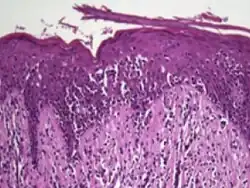

Histology

Histopathology of Pautrier microabscesses in cutaneous T cell lymphoma.

The criteria for the disease are established on the skin biopsy by the presence of the following:[18]

• Presence of cancer cells with twisted contours (cerebriform nuclei)

• In the patch and plaque stages, the cancer cells are seen in the epidermis (the most superficial layer of skin).[19] This is referred to as epidermotropism.

• Pautrier's microabcesses, aggregates of four or more atypical lymphocytes arranged in the epidermis. Pautrier microabcesses are characteristic of mycosis fungoides but are generally absent.

• In the tumour stage, the cancer cells move into the dermis (the deeper layer of skin)[19]

• Large cell transformation, where clonally identical lymphocytes in the lesion exhibit hypertrophy. In transformed cells, presence of the CD30 receptor is associated with improved survival[20]

Traditionally, mycosis fungoides has been divided into three stages: premycotic, mycotic and tumorous. The premycotic stage clinically presents as an erythematous (red), itchy, scaly lesion. Microscopic appearance is non-diagnostic and represented by chronic nonspecific dermatosis associated with psoriasiform changes in epidermis.

In the mycotic stage, infiltrative plaques appear and biopsy shows a polymorphous inflammatory infiltrate in the dermis that contains small numbers of frankly atypical lymphoid cells. These cells may line up individually along the epidermal basal layer. The latter finding if unaccompanied by spongiosis is highly suggestive of mycosis fungoides. At this stage, biopsies can reveal medium to large lymphocytes with convoluted, cerebriform nuclei in the epidermis, which are larger than the lymphocytes typically seen in inflammatory dermatoses. These atypical lymphocytes are mature skin-homing CD4+ T cells, and their presence in the epidermis is a key feature of early MF. Additionally, the cells may form microabscesses in the epidermis, known as Pautrier’s microabscesses.[16] In the tumorous stage a dense infiltrate of medium-sized lymphocytes with cerebriform nuclei expands the dermis.